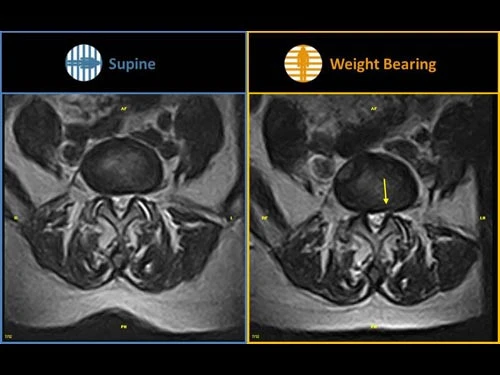

G-scan Brio представляет революционный подход в системах МРТ для всех применений, повышающий точность и надежности диагностики при обследованиях скелетно-мышечной системы. Благодаря опыту, компания Esaote разработала G-Scan, полностью переработанную систему МРТ для исследований при натуральной нагрузки пациента, которая отличается новым дизайном, новыми эргономическими функциями и новыми методами получения изображений Новая система G-scan от компании Esaote является системой магнитно-резонансной томографии, которая позволяет исследовать все суставы, а также отдел позвоночника либо в клиностатическом (лежа на спине) или в ортостатическом (с весовой нагрузкой на ноги) положении, благодаря тому, что магнит и пациент могут вращаться в диапазоне от 0 до 90 градусов. Благодаря специальной конструкции G-scan пациентов можно сканировать в положении натуральной нагрузки, что облегчает диагностику в скелетно-мышечной системы при наличии меняющихся патологий вследствие положения тела, например боли в пояснице. Многие симптомы и патологии возникают или отмечаются, когда пациент находится в положении натуральной нагрузки. Обычные томографы могут не отобразить патологию, связанную с конкретными симптомами, в то время как сканер G-scan предоставляет новую точку обзора, чтобы вы могли точно диагностировать патологию в скелетно-мышечной области, выявленную благодаря применению весовой нагрузки.